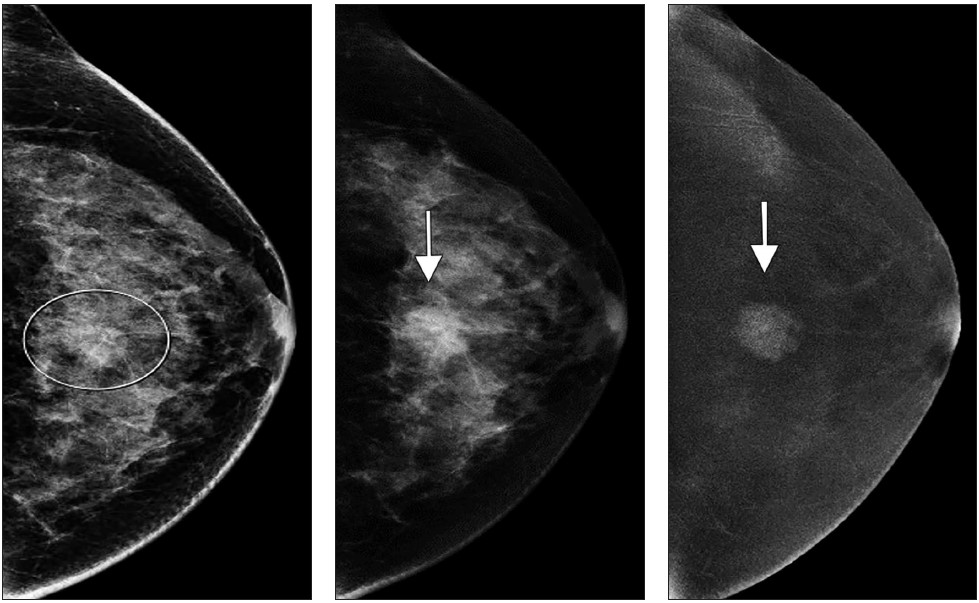

The latter mechanism most often results from strong muscular contraction that is unopposed by a counteracting fatigued muscle. In the case of rib stress fractures, the serratus anterior muscle plays a critical role [3, 4]. The serratus anterior muscle arises from the medial or ventral aspect of the scapula, with multiple slips extending anteriorly that attach to the first through tenth ribs at their middle third. The main role of the serratus anterior muscle is to protract the scapula. Importantly, this action is opposed by the scapular retractors (rhomboid muscles), which stabilize the scapula. In this situation, the serratus anterior muscle will promote an increase in the lateral diameter of the chest cavity. This mechanism can lead to abnormal stress at the middle third of the ribs in sports that involve repetitive contraction of the serratus anterior muscle, such as in elite rowing and swimming. In rowing, stress fractures are relatively common and may affect up to 12% of rowers. The peak contraction of the serratus anterior muscle occurs at the initial phase of the rowing cycle (known as “the catch”), in which the rowing oars are pulled away from the body, causing strong stabilization of the scapula by the rhomboid muscles and serratus anterior muscle. Performed repetitively, this action creates a compressive force vector directed toward the middle thirds of the ribs that can lead to stress fractures, most often affecting the fourth through eighth ribs in up to 86% of cases. If this compression is unopposed by a fatigued serratus anterior muscle, a repetitive stress injury may occur [3, 4]. Stress fractures also affect novice golfers who are still developing their technique and often strike the ground during swing strokes. Frequent ground impact force due to repetitive inaccurate strokes is thought to be transmitted to the chest wall on the leading side, causing stress fractures [5]. Additional sports in which rib stress fractures have been described include baseball, lacrosse, weightlifting, ballet, and gymnastics. MRI findings of rib stress fractures are similar to those seen in the extremities, including a well-defined linear area of low signal intensity surrounded by marrow edema, with the best contrast noted in T2- weighted fat-suppressed images (Fig. 1).

Edema in the surrounding intercostal muscles and extrapleural space is often noted [6]. As mentioned earlier, such fractures may be better depicted on oblique sagittal or coronal images that are tangential to the fracture and provide context, better showing rib portions adjacent to the fracture itself. Healing of rib stress fractures can be monitored by MRI, showing progressive improvement of marrow edema and bony bridging; however, clinical symptoms may persist even though the fracture appears healed on imaging.

Areas that may be affected by costal cartilage injury include the sternochondral junction, midsubstance of the costal cartilage, and costochondral junction. Most commonly, such injuries affect the relatively immobile upper rib cage (first to third costal cartilages) and are due to rotation injury and/or excessive axial loading (such as in weightlifting). Lesions affecting the lower rib cage (fourth through eighth costal cartilages) typically result from direct impacts, such as seen in contact sports (hockey, football, rugby, and martial arts) [8]. An important anatomic feature of costal cartilage is the presence of a central cavity that is best seen on CT images as a zone of lower attenuation tracking along the structure [9]. A predominance of blood vessels, loose connective tissue, macrophages, and fat exist within this area. Although this zone resembles a bone marrow cavity, no marrow cells or lineage is present. Anatomic studies suggest this central channel in costal cartilage is more akin to nutrient channels because of the dominant feature of high vascularity. The presence of a dense vascular network in this portion of costal cartilage predisposes to significant bleeding in the event of fractures. A common feature in costal cartilage fractures is the presence of an associated hematoma of the chest wall, which can lead to clinician suspicion of neoplastic masses. Scrutiny of the area using thin-slice CT may reveal a linear discontinuity of the costal cartilage adjacent to the suspected mass, increasing the likelihood of a trauma-related cause. Patient history may help direct the radiologist, as a traumatic event related to lifting or direct impact may have occurred, possibly resulting in subsequent pain and a local mass (Fig. 2).

MRI provides excellent contrast to show costal cartilage fractures, which will appear as linear areas of high signal intensity against a background of low-signal-intensity costal cartilage [8]. Although MRI has superb spatial resolution and contrast, its relatively higher cost and susceptibility to respiratory motion artifacts decrease its effectiveness, when compared with CT. Ultrasound may also prove useful, given the superficial location of costochondral structures, and may show a focal stepoff at the fracture area [1]. As previously mentioned, costal cartilage injuries may occur at the sternochondral or costochondral junctions. At these locations, chondral and adjacent bone marrow edema may be present on MRI and represent the dominant findings related to traumatic injury. Treatment of costal cartilage injuries include NSAIDs, taping and immobilization belts, and rest for 2–3 weeks. In certain situations, such as treatment of professional athletes, pain can be mitigated by local injections of anesthetic [8]. An important differential diagnosis to consider when entertaining the possibility of a costochondral injury is Tietze syndrome. In this rare entity, inflammation of the sternochondral junction (the most common symptom) can occur spontaneously and lead to focal pain without any specific initiating event. The cause of Tietze syndrome is uncertain, and the condition usually affects younger patients (< 40 years old). On MRI, this entity may show edematous change surrounding the sternochondral junction, which is best seen on fat-suppressed T2-weighted images [10]. CT may not provide enough tissue contrast for adequate detection. Given that Tietze syndrome is usually self-limited, its treatment includes rest, NSAIDs, and local anesthetic injections in refractory cases.